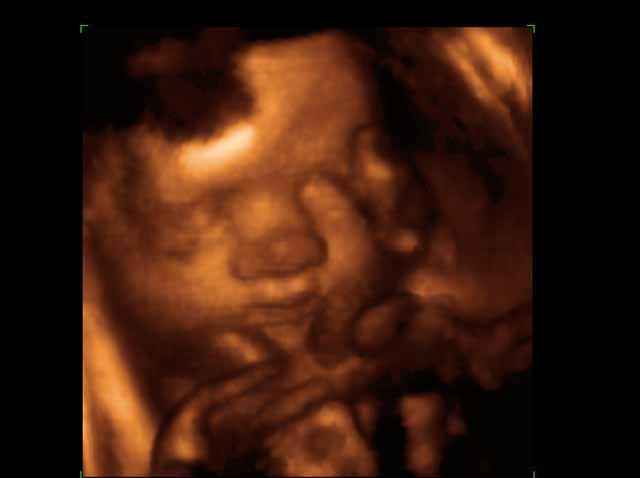

- 3D Fetal Profile Ultrasound Scan Photos

3D Fetal Face Ultrasound Scan Photos | Dr N Layyous